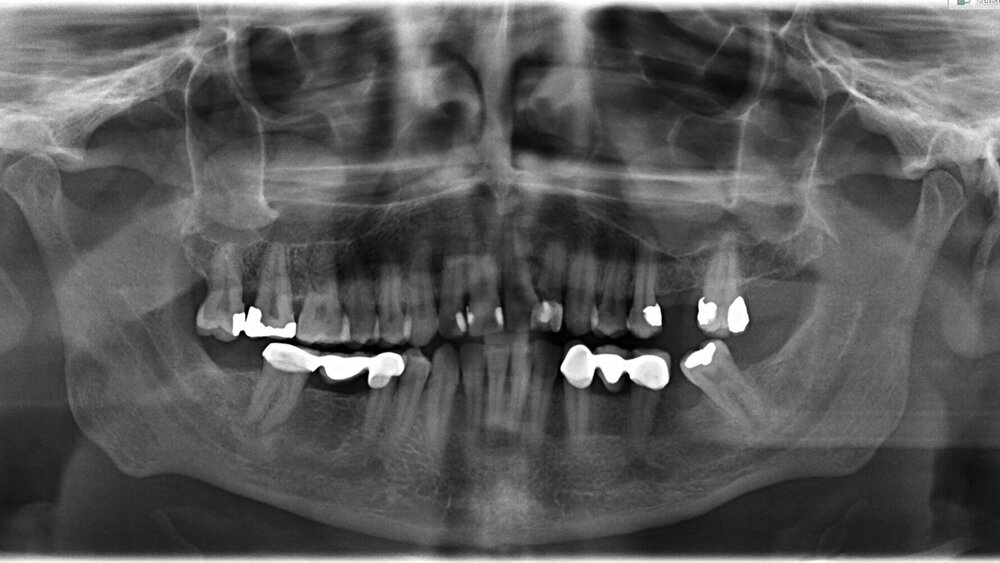

Ein 40-jähriger Patient wurde zur Extraktion der Zähne 17 und 18 überwiesen. Aus dem Jahr 2018 lag eine Panoramaschichtaufnahme vor, auf der zystische Veränderungen in beiden Kieferhöhlen (Regio 17 sowie 26) sichtbar waren (Abbildung 1). Als Verdachtsdiagnose wurde „Schleimretentionszysten" in der Patientenakte eingetragen, bevor ein aktuelles OPG angefertigt wurde.